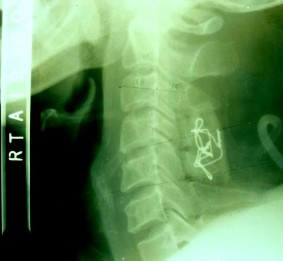

SAU MỔ 4 THÁNG: tình trạng KHX vẫn tốt, không di lệch thứ phát, không giãn chỉ, không đứt chỉ.